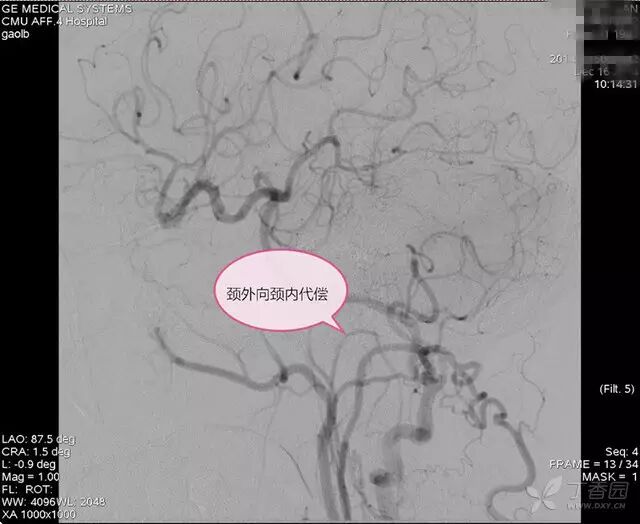

DSA:右锁骨下动脉起始部狭窄,狭窄率 96%,右椎动脉血流前向,右胚胎性大脑后动脉,左颈总动脉闭塞,左后交通动脉开放,后循环经左后交通动脉向左颈内动脉代偿,左甲颈干经左颈外动脉向左颈内动脉供血区代偿(图 1~4)。

图 3. 颈外向颈内代偿